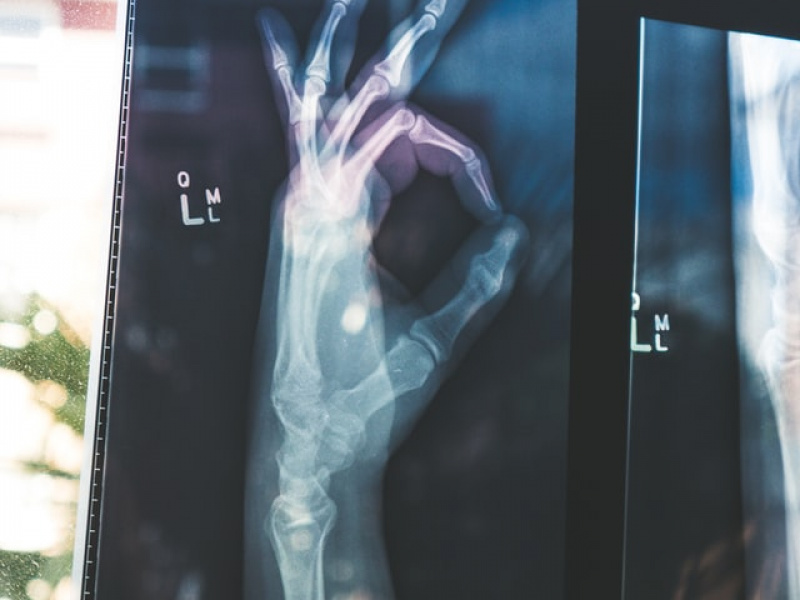

Préparer mon examen d'imagerie médicale

Afin que votre examen se passe dans les meilleures conditions possibles, il est nécessaire de se préparer correctement